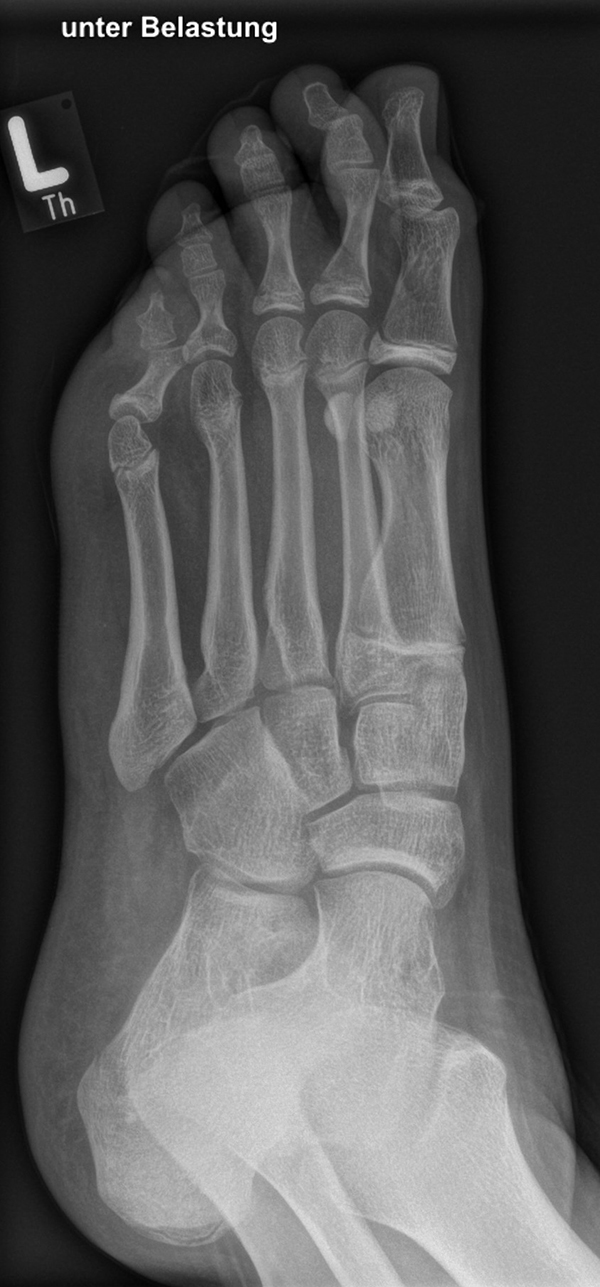

Damit die minimalinvasive Fußchirurgie zur Korrektur kindlicher oder jugendlicher Fußdeformitäten erfolgreich angewendet werden kann, erfordert die präoperative Diagnostik Röntgenbilder in drei Ebenen am stehenden Fuß. Röntgenbilder ohne Belastung des Fußes sind nicht zielführend. Im Fall von schweren Rückfußdeformitäten wird das obere Sprunggelenk in die radiologische Diagnostik mit einbezogen in Kombination mit der Rückfußaufnahme unter Belastung („Saltzman View“). Das OSG wird in zwei Ebenen geröntgt. Die streng seitliche Aufnahme des OSG kann bei den komplexen Fußdeformitäten mit der seitlichen Aufnahme des Fußes unter Belastung kombiniert werden. Das reduziert die diagnostische Strahlenbelastung der Kinder.

Indikationen für die beschriebenen Röntgenaufnahmen sind Klumpfußdeformitäten zur Beurteilung eines „flat top talus“ oder neurologische Grunderkrankungen mit varischer Fersenstellung wie zum Beispiel bei HSMN (Hereditäre Sensorische Motorische Neuropathie).